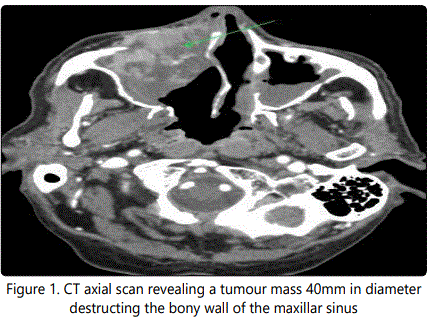

The opthamic-out patient antibiotic treatment did not result in any improvement and for progression of this resistance he was referred to ENT. A CT was done which revealed a tumour mass in the right maxillary sinus, 4x5 cm in size, destructing an anterion bony wall and invading an orbit and a nasal cavity. (Figures 1-2) Surgical exploration followed via approach secundum Denker. A macroscopically greyish-white ovoid tumoar with multiple grooves 38x29x18 mm was subtotally removed (except periorbit). Histopathologic samples were processed by the standard formol-paraffin technique and showed malignant epithelial tumour with cells growing in trabeculae, with eosinophilic finely granular cytoplasm, infiltrating the respiratory mucosa. Immunohistochemical analysis proved expression of Hepatocyte (Monoclonal Mouse Anti-Human Antibody, clone OCH1E5, Dako, USA), considered specific for hepatocellular differentiation.

A CT is usually the first choice of radio diagnostic method which displays generally enhancing tumourous mass, possibly with osteolysis. The CT scan is mostly typical for malignancy, distinguishable from benign or inflammatory pathology but not from primary sinus carcinoma. An MRI completes information about soft tissues (metastasis is hypo intense on T1 and hyper intense on T2).